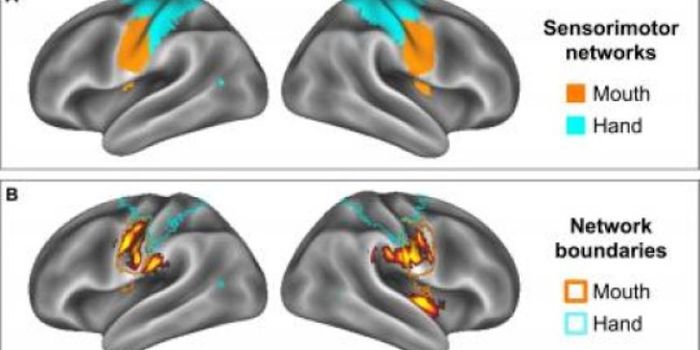

JUL 07, 2015NeuroscienceWhat is it about our brain wiring that makes it easy to pick up a pen or remember the lyrics of a song, each at the appr ...